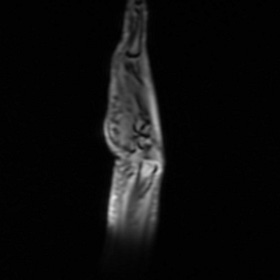

A barrage of emergency room visits, x-rays, MRIs, steroid treatments, antibiotic treatments, autoimmune condition tests, casts & wrist splint applications, scheduled-then-aborted emergency surgeries, orthopedist visits, and hand therapy sessions ensued. A variety of specialists & surgeons threw themselves at the mystery of my hand, intrigued by the challenge and palpably concerned for me.

Eventually, my team figured out that I had ruptured my FPL tendon, which connects the muscles of the forearm to the thumb, and the injury had somehow become infected and filled with fluid, blocking the rest of my hand from working for a while. There wasn’t any single cause that anyone could pinpoint, but when one of my emergency surgeons diagnosed me as just about as hypermobile as a human being can be (“Holy shit!” was his reaction to my Beighton Score results), everybody agreed that casual abuse of my freakishly bendy body was probably a major factor.